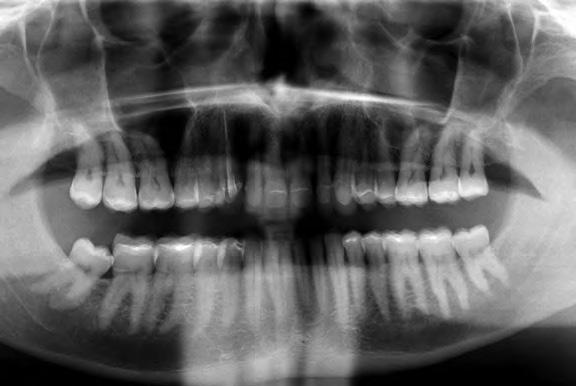

Dr. Miguel Stanley, dr. Ana Gomes Paz, dr. Inês Miguel (Portugália) Dr. Christian Coachman (Brazília) 1. ábra: Kiindulási állapot (frontális irányból). 2. ábra: A kiindulási állapotról okkluzális irányból készített felvétel (felső állcsont). 3. ábra: A kiindulási állapotról okkluzális irányból készített felvétel (alsó állcsont). 4. ábra: A kiindulási állapotról készült panorámaröntgen felvétel (2015).

2015-ben egy 47 éves férfi páciens állkapocs-ízületi panaszai miatt kereste fel a rendelőnket. Ezen felül esztétikai problémát jelentett számára, hogy az egyik felső nagymetszőfogán lévő héj eltört (1-3. ábrák). A klinikai és radiológiai vizsgálatot követően megállapítható volt, hogy a páciens kifejezett bruxizmusa miatt csökkent a harapási magassága, és jelentős mennyiségű saját foganyagot abradált el (4. ábra)

Szájterpesz használata mellett digitálisan intraorális fotók készültek a páciensről mind frontális, mind laterális és okkluzális irányokból. További fotók is készültek a páciensről egy digitális tükörreflexes kamera segítségével (frontális és laterális irányból, valamint 45 o-os szögből). Mindkét állcsontról digitális lenyomat készült egy intraorális szkenner segítségével (Care stream 3500). A maximális-interkuszpidációs helyzetet (IKP) szintén a Carestream 3500-as készülék felhasználásával rögzítet -